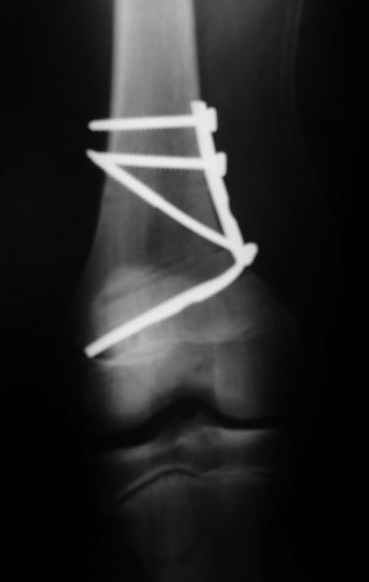

На своем горьком опыте убедился, что синтезировать мыщелковые импрессионные внутрисуставные переломы б\б кости без костной пластики - дело неблагодарное, рецидивируе деформация, мыщелок всегда *проваливается*. Чистые split type переломы можно ограничиваться и одной только межфрагментарной компрессией.

Может стоит сначала добиться сращения наружного мыщелка бедра( костная пластика) и коррекции оси?

Мне представляется, что прогрессирующий вальгус и обусловлен несросшимся переломом мыщелка бедра (томограммы -зона межфрагментарного склерозирования), а циклические нагрузки на сустав во время ходьбы усугубляют ситуацию. Как вы думаете, в этой ситуации насколько вероятен риск развития аваскулярного некроза мыщелка бедра?